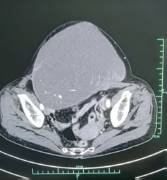

此次接受手术的患者为中年女性,2年前发现“腹部肿块”,大小如“拳头”,经化学治疗后效果不佳。近半年来,腹部肿块逐渐增大,患者日渐消瘦,近日更出现肠梗阻症状,严重威胁生命健康。经CT复查发现,肿瘤复发且病灶位于腹腔复杂区域,紧邻肠管、输尿管、大血管及既往手术瘢痕组织,局部粘连严重,解剖结构紊乱。

术中可见,肿瘤与小肠、结肠及侧腹壁形成致密粘连,部分区域甚至包裹输尿管及髂血管分支。团队采取“先易后难、先外围后核心”的策略,首先游离肿瘤周边相对正常的肠管及系膜,逐步暴露肿瘤边界;对于与血管粘连处,采用“钝锐结合”的精细分离技术,逐一辨认血管分支,避免误伤;针对紧贴输尿管的肿瘤组织,仔细分离并保护输尿管血供与走行,确保其功能不受影响。

经过近4小时的紧张操作,最终完整切除直径约17cm的复发肿瘤,术中出血不足50ml,最大程度地保护了周围重要器官及血管功能,术中患者生命体征平稳。